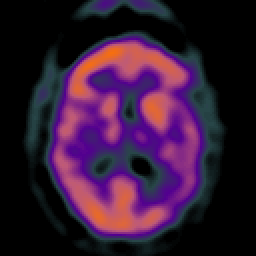

Subdural Hygroma,overlay -- Slice #27

[Home][Help][Clinical] Slice 27